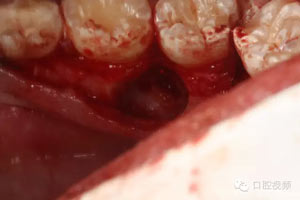

圖7.通過CBCT準(zhǔn)確定位,暴露35部分牙冠。

圖8.繼續(xù)去骨、暴露整個(gè)35牙冠。注意牽拉力度。